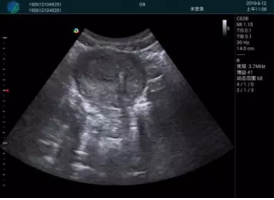

清晰顯示孕囊,通過軟件包計算孕齡7w+6d

M20實時引導,術中清晰顯示孕囊被破壞和抽吸針的過程,清晰顯示吸引針

抽吸結束后縱切子宮,孕囊已被完全抽吸,未見明顯殘留

橫切子宮,發(fā)現右側宮腔靠近宮角處有少許脫模樣殘留

M20引導下,抽吸針找到右側宮角處再次清掃

二次抽吸后再次進行超聲檢查,宮腔未見殘留,宮腔線清晰顯示